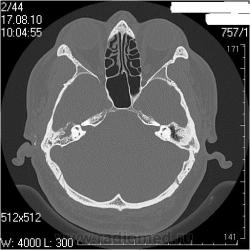

Левая височная кость

Наружный слуховой проход: конфигурация обычная, просвет не сужен, костные стенки ― ровные, четкие.

Сосцевидный отросток: тип строения склеротический.

Воздушные полости среднего уха: пневматизация нарушена за счет пристеночных мягкотканных (41едН) патологических структур; размеры аттика, адитуса и антрума в пределах нормы. Ширина аттика (на уровне латерального канала) ― 5,7мм (N=6.4-7мм), адитуса ― 3,5мм (N=3,1-3,3мм), антрума ― 6,4мм.

Костное устье слуховой трубы: пристеночные мягкотканные патологические структуры.

Слуховые косточки прослеживаются

Внутреннее ухо: размер, форма, положение, плотность и контуры элементов структур внутреннего уха не изменены.

Внутренний слуховой проход: конфигурация не изменена, контуры ровные, четкие, ширина ― 4,3мм (N=4-6мм)

Заключение: КТ- признаки двустороннего хронического среднего отита: склеротические изменения больше выражены в левом сосцевидном отростке; мягкотканные патологические структуры в воздушных полостях среднего уха больше выражены справа; блок костного устья правой слуховой трубы; неполный блок костного устья левой слуховой трубы

Андрей Юрьевич, извиняюсь за столько вопросов,тема для меня неизведанная, но пузырьки воздуха в патологическом компоненте/субстрате/массах слева не могут быть признаком гнойного процесса?

Гнойного, т.е. газообразующего? Нет. Это атмосферный воздух. Он должен быть в барабанной полости в норме, а тут и патологического содержимого меньше, чем справа + неполный блок слуховой трубы + перфорация барабанной перепоки

А засада (что НЕ ТАК), для меня здесь вот в чем. У пациента клиника левостороннего отита (многолетний анамнез, отделяемое из уха, перфорация перепонной барабанки при отоскопии), а справа клиники нет совсем. После КТ ЛОРы дописали рубец на правой перепонке, и выписали + с адгезивныи отитом справа (хотя при адгезивном отите КТ-картина должна быть несколько иная).